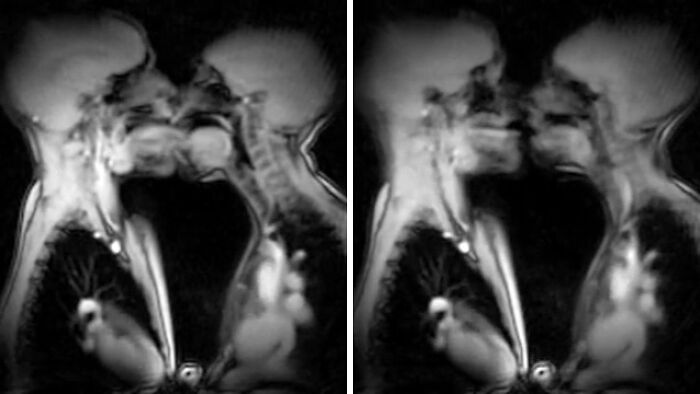

This Is What Kissing In An Mri Scan Looks Like

MRI scans showing rare and surprising body features of two people kissing, highlighting unique internal anatomy.

bendubberley_ Report